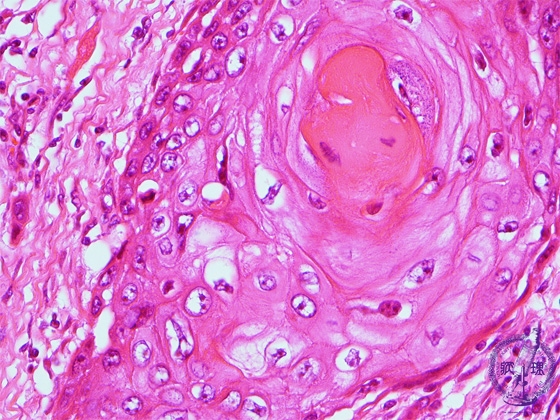

- š(5)Squamous cell carcinoma (larynx)

Microscopic view (high power view): Carcinoma cells have eosinophilic cytoplasm, compatible with keratinization. Structures with the appearance of a multi-layered onion like cross section are known as gkeratin pearlsh and are typical of keratinizing (squamous cell) carcinoma.